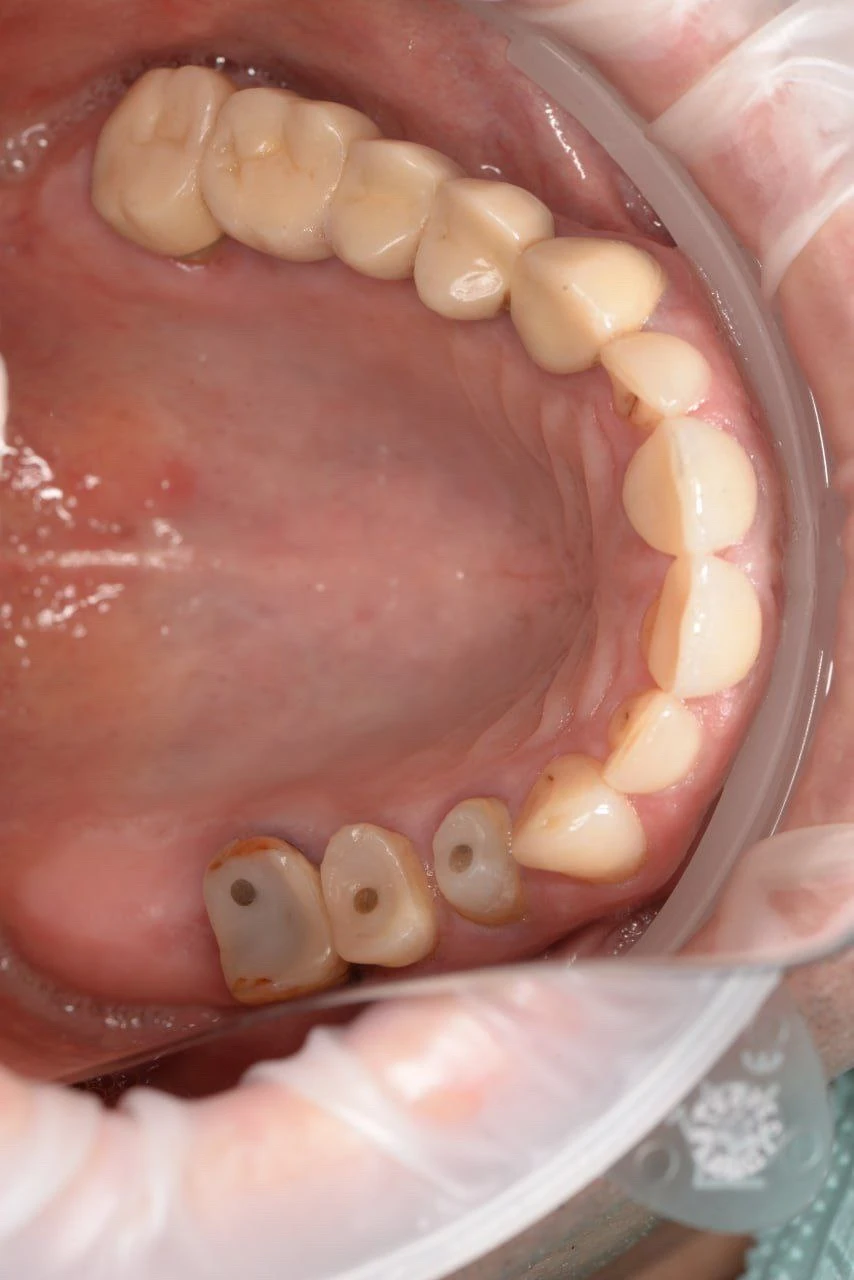

Цирконієва коронка 45 та цирконієва коронка 46 на імпланті